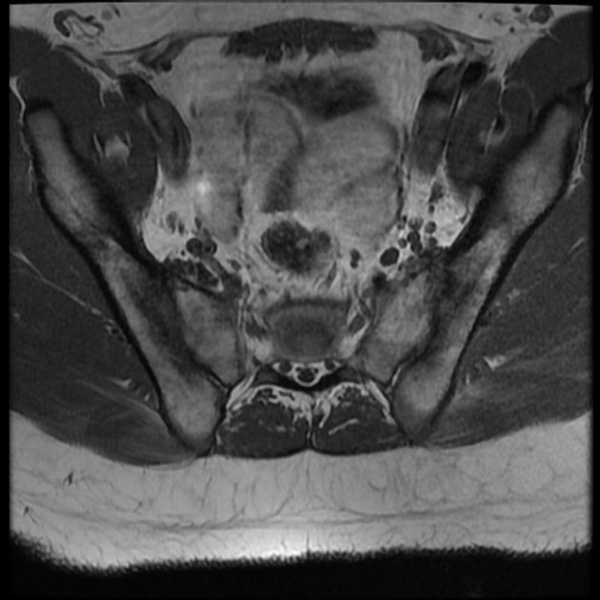

Sau đây là một số hình ảnh viêm cột sống dính khớp trên X-quang: